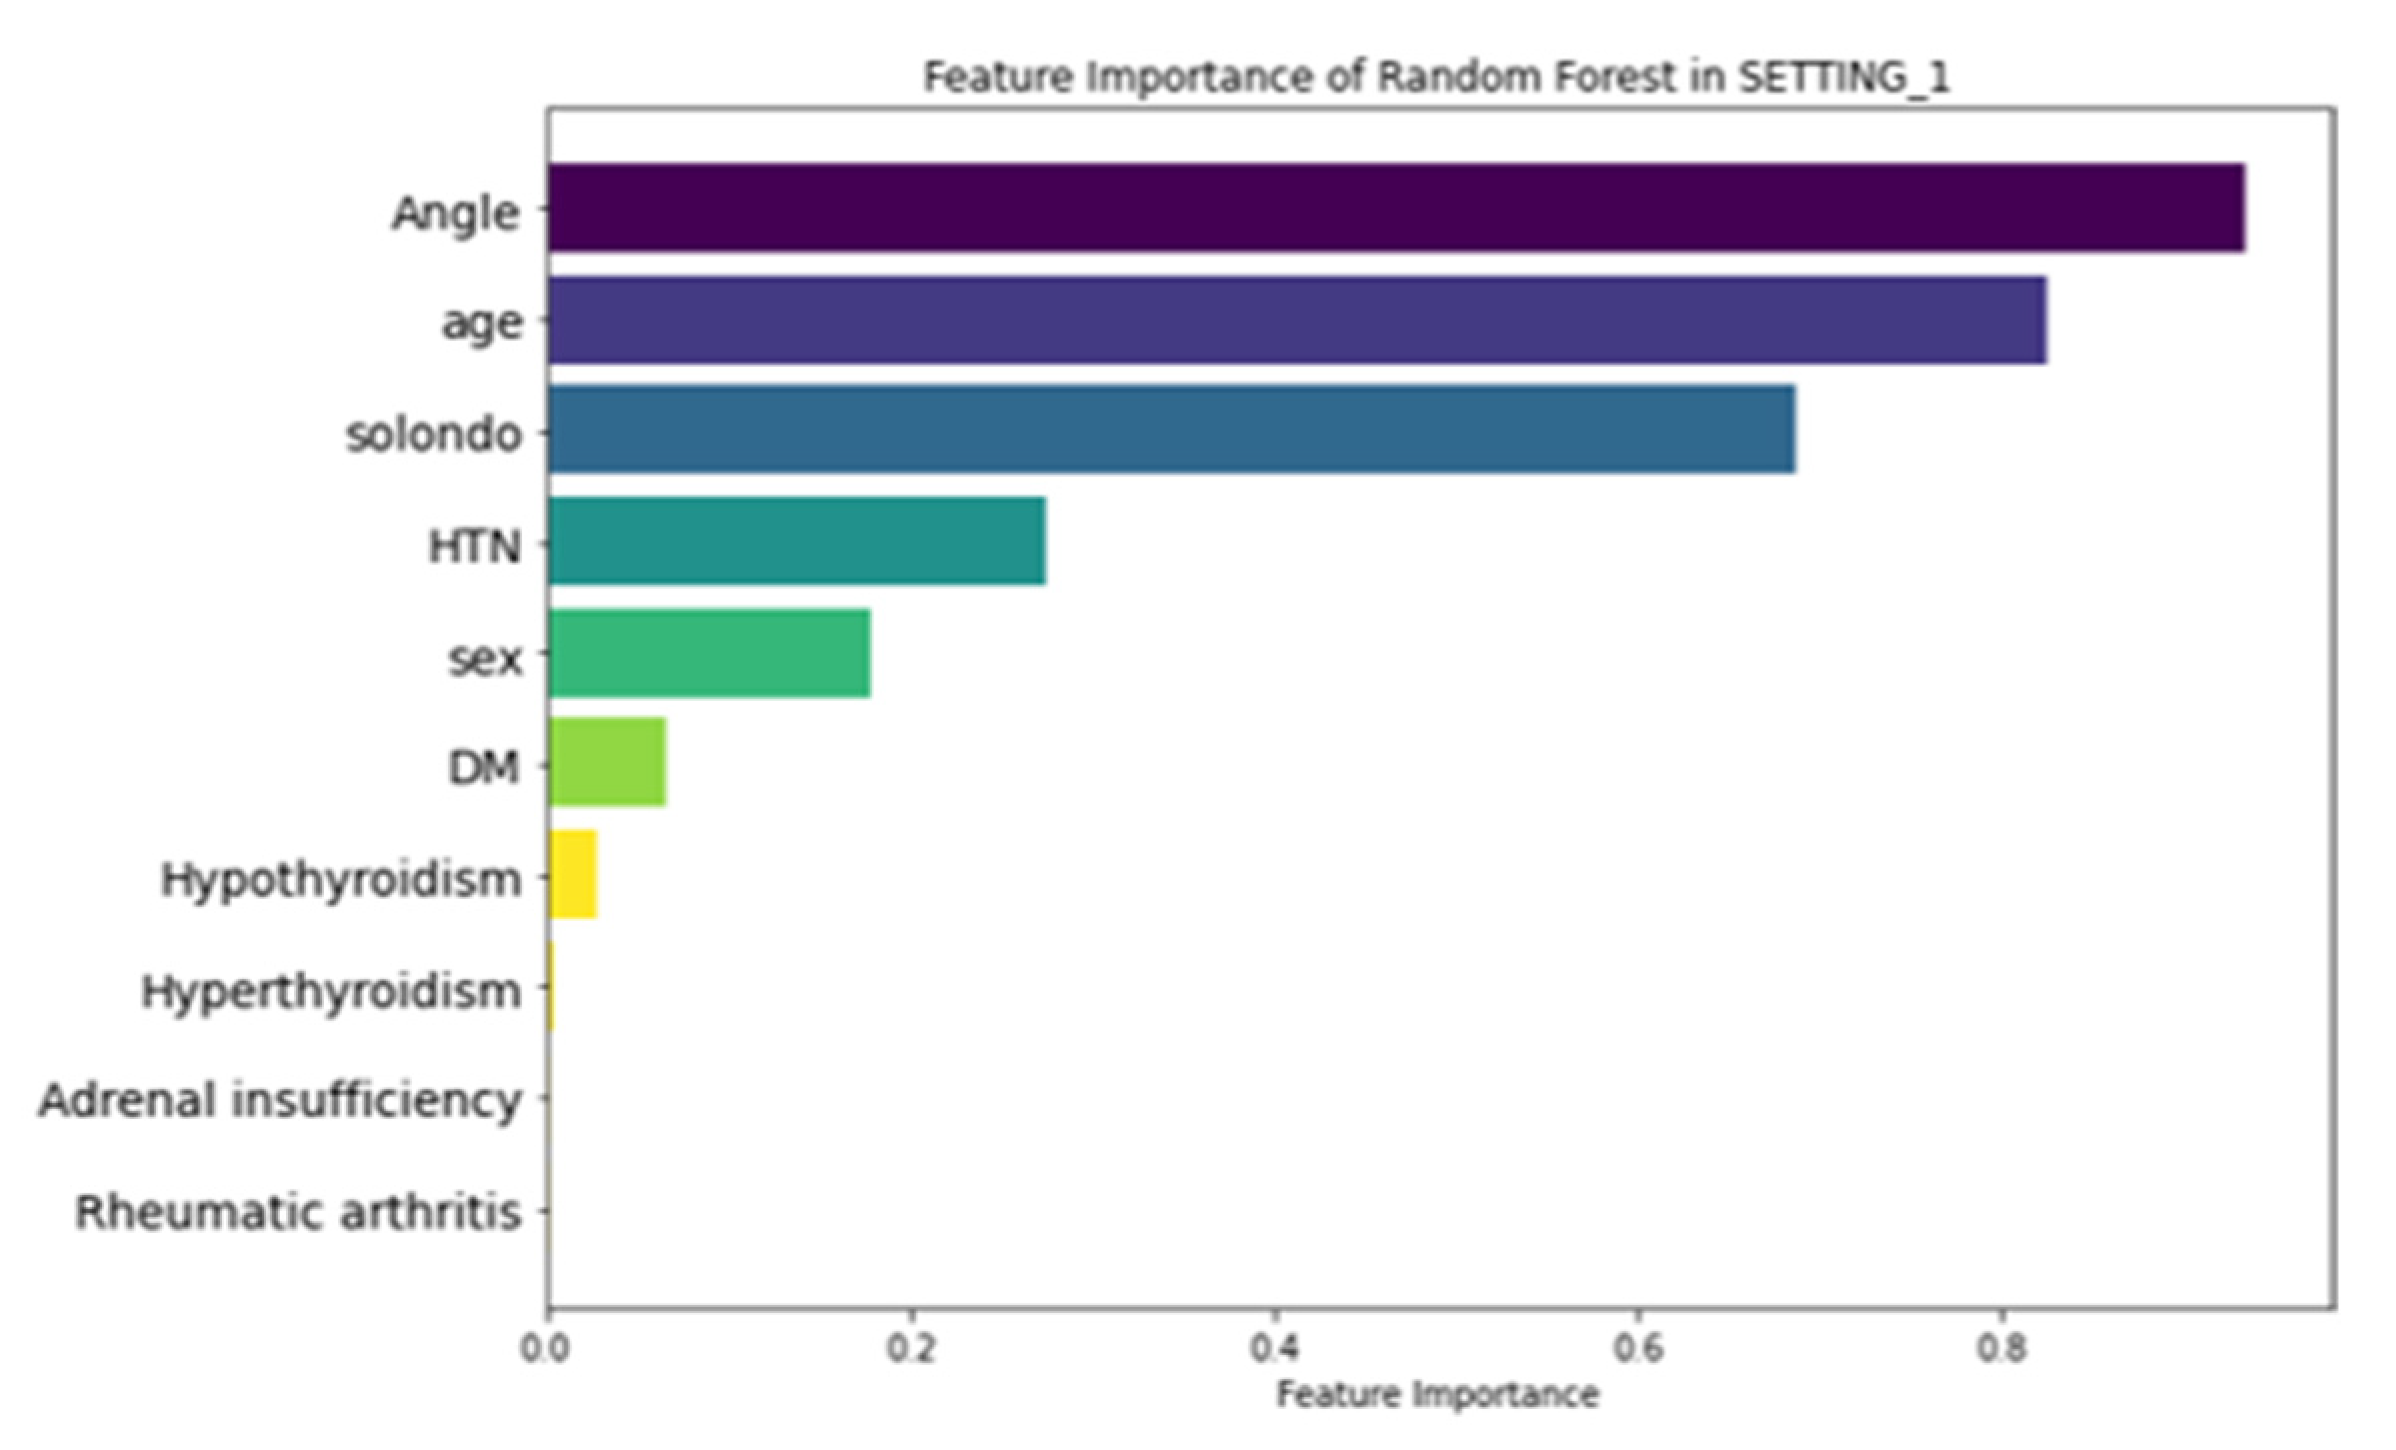

3.3. Feature Importance

3.4. LIME Analysis